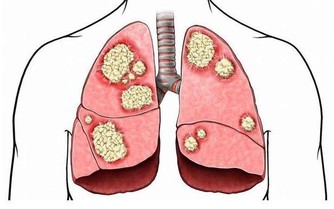

7、腦缺氧

發生腦動脈硬化、血管脂質沉積等腦血管疾病時,會降低血腦屏障的通透性,導致腦組織缺血、缺氧,出現嗜睡。大腦長期缺氧還可能產生一系列的精神、神經狀。如記憶力下降、行為異常、個性改變等。